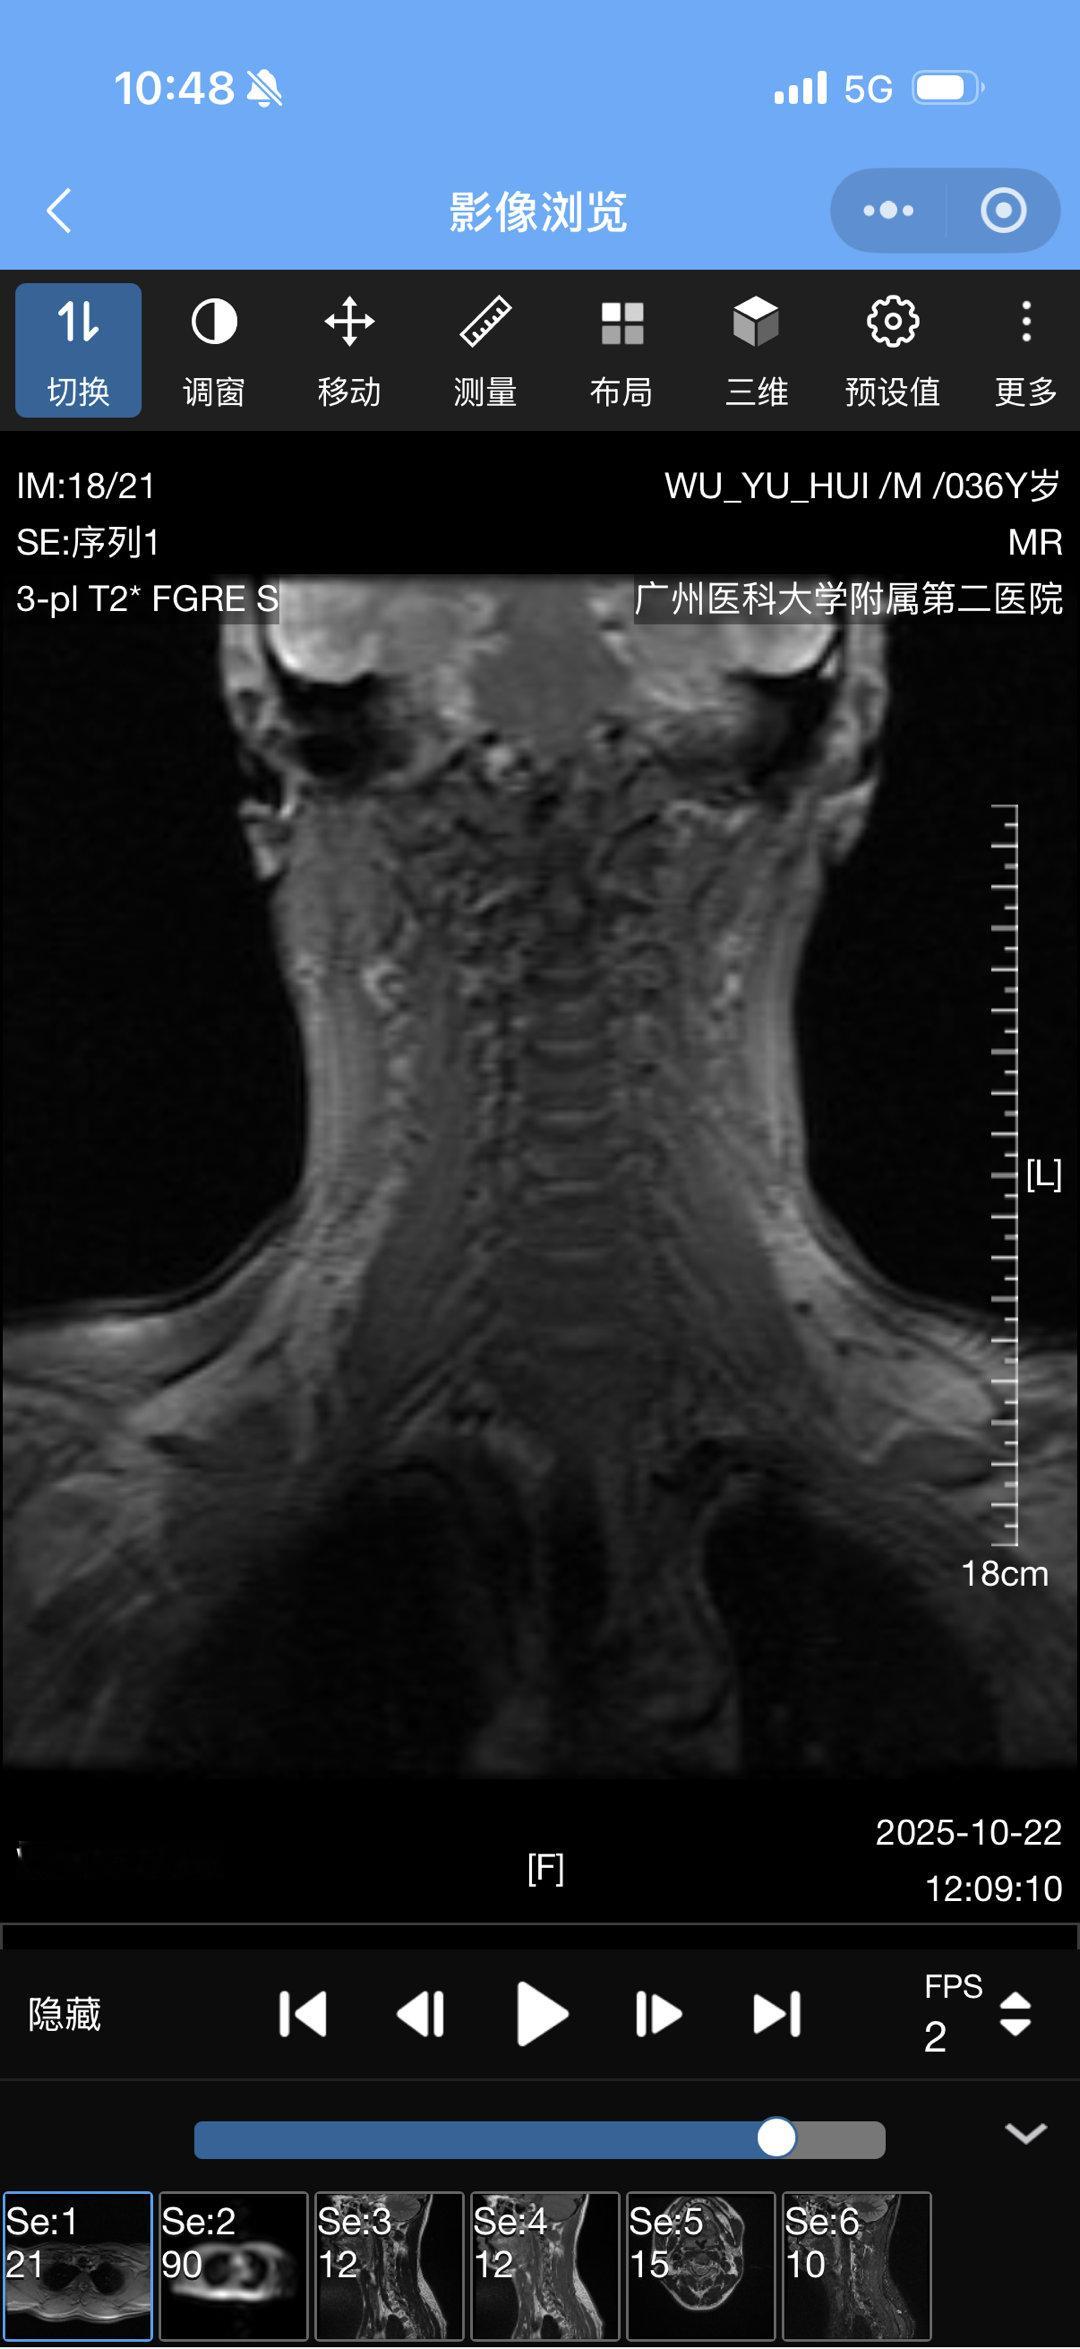

结果出来了颈椎间盘4 节突出还有救吗[捂嘴哭]幕后工作十几年的代价

结果出来了

颈椎间盘4 节突出

还有救吗[捂嘴哭]

幕后工作十几年的代价